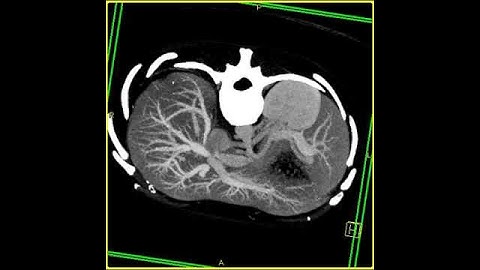

Abdomen: Pancreas: Pancreatic cancer : 3D mapping using volume rendering and MIP: Axial